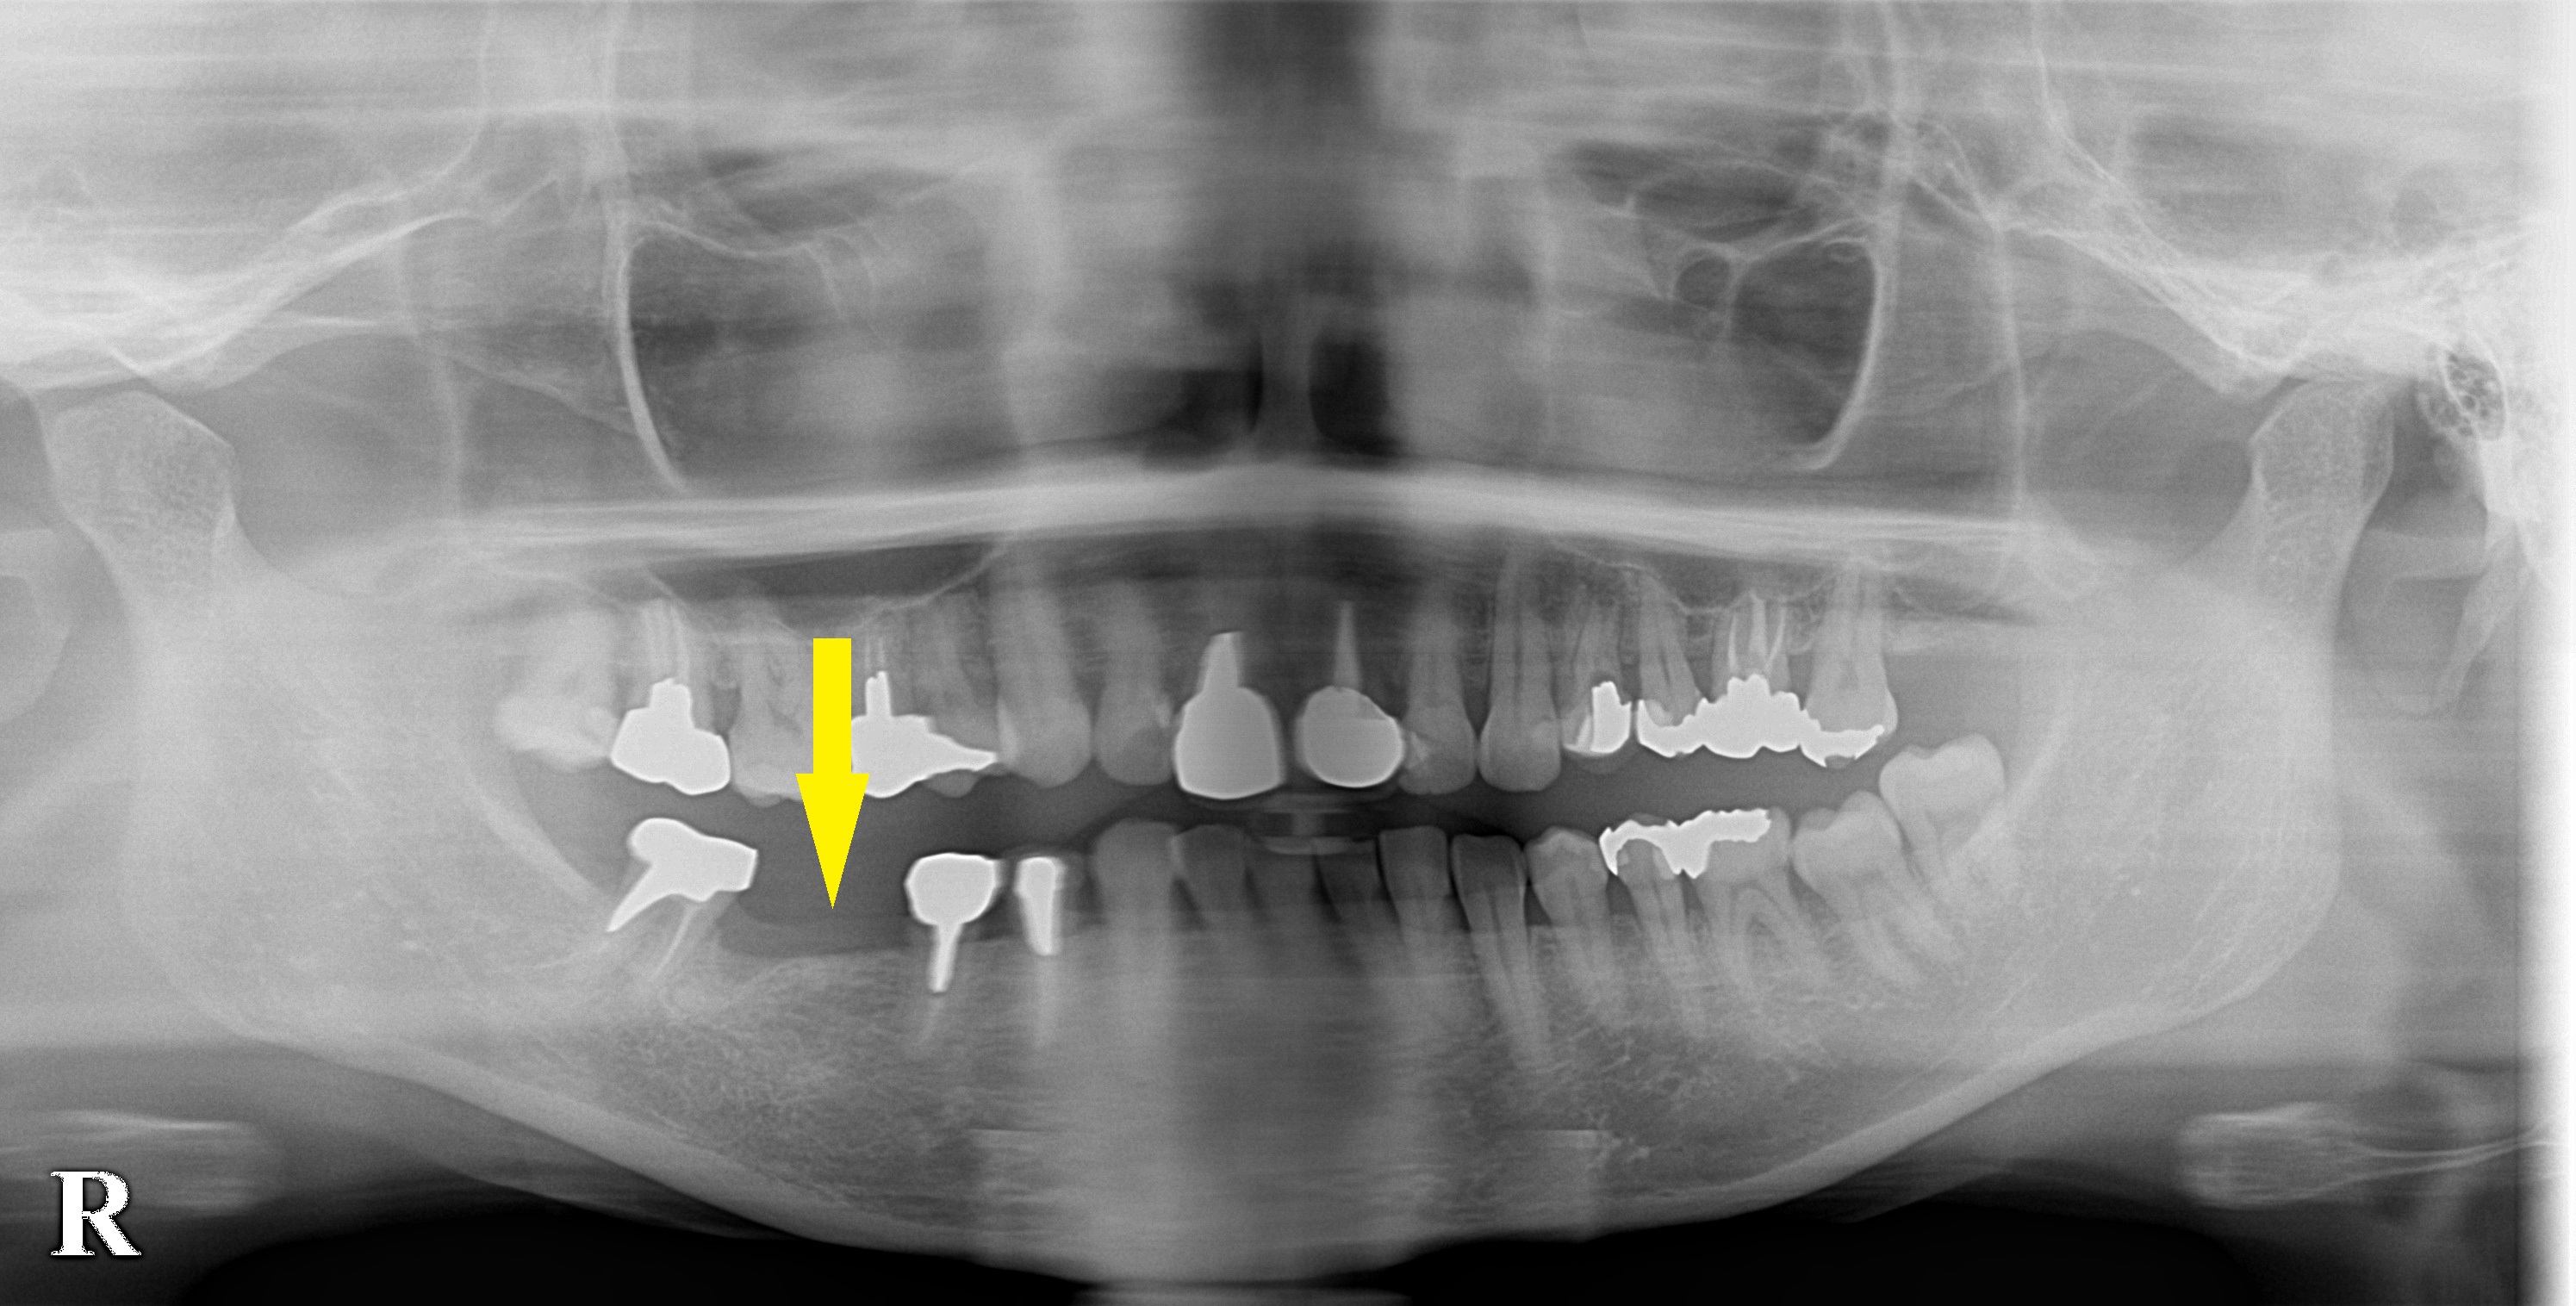

右下顎第一大臼歯がダメになって数か月前に抜歯されたそうです。

抜歯した部位の治癒は問題なく、骨量も十分でしたので、本日インプラント埋入術を行いました。